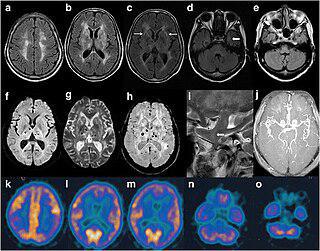

Фатальная семейная бессонница — редкое неизлечимое наследственное, нейродегенеративное (доминантно-наследуемое) прионное заболевание, при котором больной неизбежно умирает от бессонницы. Известно всего 42 семьи, поражённых этой болезнью.